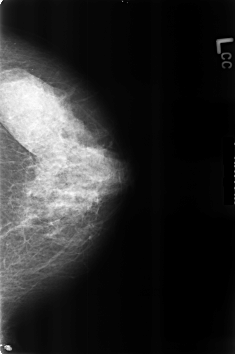

ics_version 1.0 filename B-3226-1 DATE_OF_STUDY 7 7 1998 PATIENT_AGE 51 FILM FILM_TYPE REGULAR DENSITY 3 DATE_DIGITIZED 13 7 1998 DIGITIZER LUMISYS LASER SEQUENCE LEFT_CC LINES 4600 PIXELS_PER_LINE 3048 BITS_PER_PIXEL 12 RESOLUTION 50 NON_OVERLAY LEFT_MLO LINES 4528 PIXELS_PER_LINE 3088 BITS_PER_PIXEL 12 RESOLUTION 50 NON_OVERLAY RIGHT_CC LINES 4608 PIXELS_PER_LINE 3112 BITS_PER_PIXEL 12 RESOLUTION 50 OVERLAY RIGHT_MLO LINES 4624 PIXELS_PER_LINE 3088 BITS_PER_PIXEL 12 RESOLUTION 50 OVERLAY |